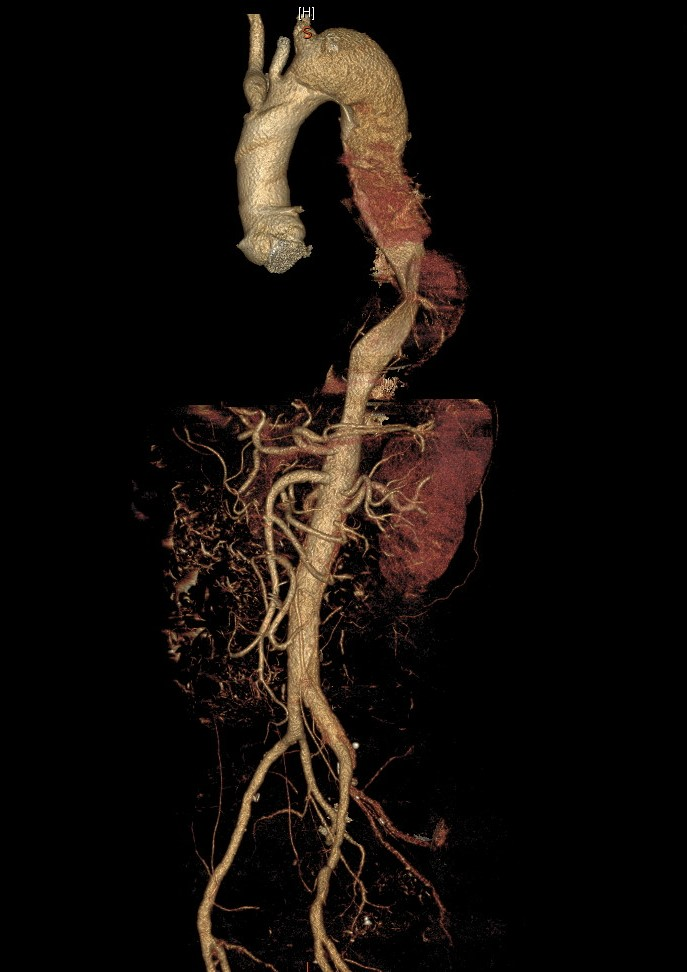

男性患者,58岁,因反复发热2周就诊。2周前,患者无明显诱因出现发热,为驰张热,最高体温39℃,无寒战、咳嗽咳痰、头晕头痛、腹痛腹泻、尿频尿痛等不适,无胸背痛、喘憋、呼吸困难、心悸、大汗等不适。就诊附近医院化验白细胞升高,口服头孢抗生素,体温降至正常后停药,2天后再次出现上述发热情况。再次就诊时检查胸部CT时发现胸主动脉增宽,未见明确肺部感染征象。进一步行主动脉CTA发现Stanford B型主动脉夹层(如图1)并收治入院。入院后超声心动图检查,提示主动脉瓣占位(赘生物不除外)、重度关闭不全(如图2-A,B,C);血培养发现星座链球菌,考虑感染性心内膜炎,瓣膜赘生物形成。

(图1)主动脉夹层(Stanford B型)累及左侧锁骨下动脉